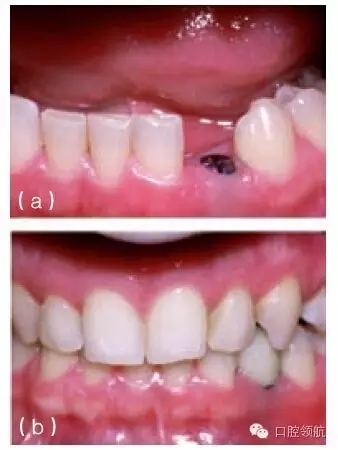

在可視性較高的無牙區(qū)植入種植體時,要想獲得理想的軟組織外形和鄰間牙齦乳頭高度是一個挑戰(zhàn)。可能存在各種各樣的問題:牙與牙之間黑三角間隙的存在(圖10.22a,b);邊緣組織的厚度大于鄰牙牙齦邊緣厚度(圖10.23);與相鄰或?qū)?cè)的天然牙相比,軟組織邊緣的根向位置可能不在同一高度上(圖10.24);牙齦乳頭可能不具備最理想的外形或高度(圖10.21~圖10.25);由于軟組織退縮造成臨床牙冠長度改變或金屬暴露(圖10.26a,b)。

圖10.22 (a)金屬烤瓷冠的唇側(cè)觀,可見近中觸點下方一較小的黑色間隙,如果有齦乳頭的充填這些間隙就看不到。(b)種植體植入到尖牙區(qū),該區(qū)可見到明顯的牙槽嵴吸收和牙齦萎縮。在種植體冠的頸部可見到相對較大的黑色間隙。